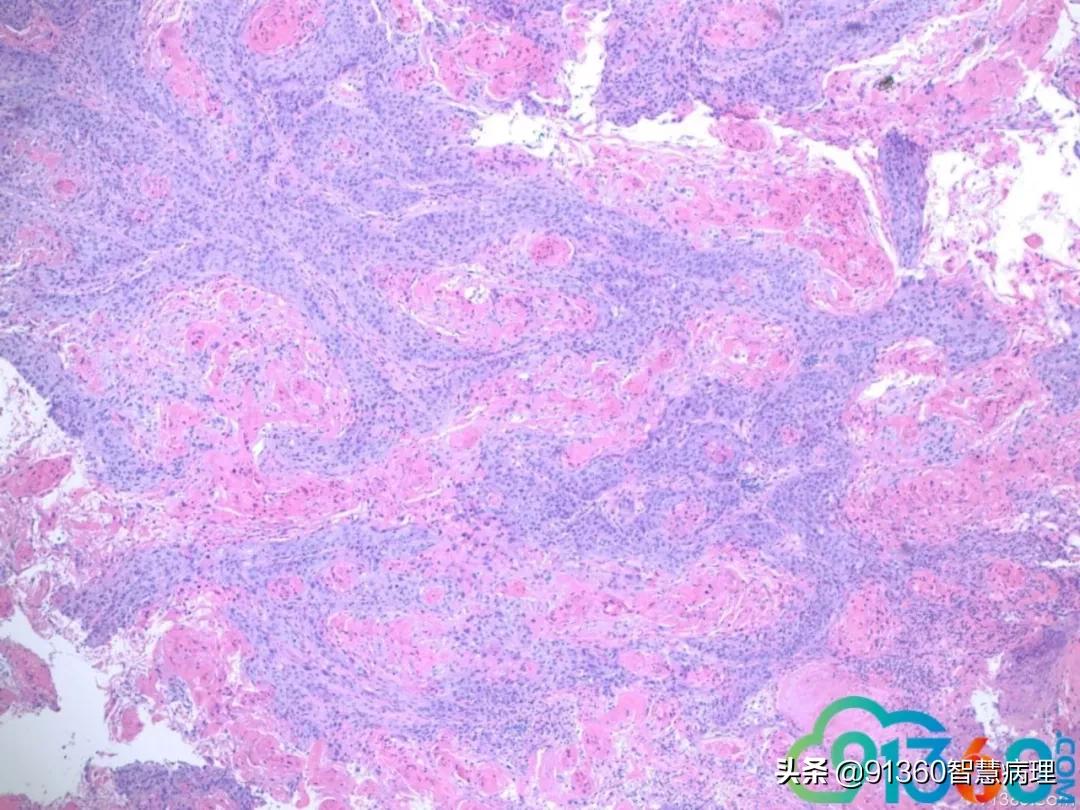

喻明芙 和Pap 符合@赵澄泉UPMC 谢谢 赵澄泉 组织切片有假象,但局部可有明显浸润 喻明芙 这就是Pap中看到的异常角化细胞

喻明芙 @赵澄泉UPMC 先给大家机会看看组织学@赵澄泉UPMC 谢谢分享 赵澄泉 @阎培莎 @诸城市妇幼保健院王瑞辉 群管 @姜锦贵,江苏金湖医院 @喻明芙/病理/康州 @彭振武(广州安必平公司) @厦门motic孙煜昀 @廖新波(JMC-NY) @舒兰市中医院病理科宋晓华 细胞学是atypical parakeratosis cells. 这是为什么大家觉得很难报LSIL, HSIL, cancer, even ascH. 经验:如果这种细胞很多尤其HPV阳,一定要想着鳞癌的可能,一定和临床沟通,组织活检,不要漏掉病人,这例我报的ASCH,备注强调病人需活检。实际工作中组织学对照是学习细胞学最好老师 石丽华 @赵澄泉UPMC 学习了谢谢老师分享这种角化不认识,实际工作中易漏掉 孙煜昀 乳头状的鳞状上皮病变,低级别时也可以出现出现这种细胞形态。两者鉴别主要是坏死和里面混杂高级别细胞,赵老师给的病例细胞学没有明确高级别细胞,报ah可以。但是要打的更高,可能需要更多视野的支持 Andy K (纽约) 这种dyskeratotic cells是高度怀疑鳞癌的

喻明芙 我学习的麟癌有3大特征:肿瘤素质(非常难认),异常角化,和异形麟装上皮有核仁。反过来看,这里Pap缺第三,但要怀疑。我会写到Note 孙煜昀 支持老师看法红圈的细胞对照的很好,绿圈的细胞在细胞学没有对应,只有我打剪头的一个细胞,所以才加大了难度可能在肿瘤表面全是角化不全的细胞。很难取到下面的肿瘤主体